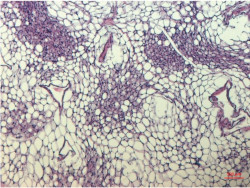

Descubren que sólo un subtipo de célula grasa humana responde a la estimulación de la insulina

Es bien sabido que las células grasas pueden influir en la sensibilidad a la insulina. Ahora, investigadores del Instituto Karolinska, en Suecia, han descubierto que existen tres subtipos diferentes de células grasas maduras en el tejido adiposo blanco pero que sólo una de ellas, llamada AdipoPLIN, responde a la insulina. Los hallazgos, publicados en la revista `Cell Metabolism`, pueden ser relevantes para futuros tratamientos de enfermedades metabólicas como la diabetes de tipo 2, según los investigadores.